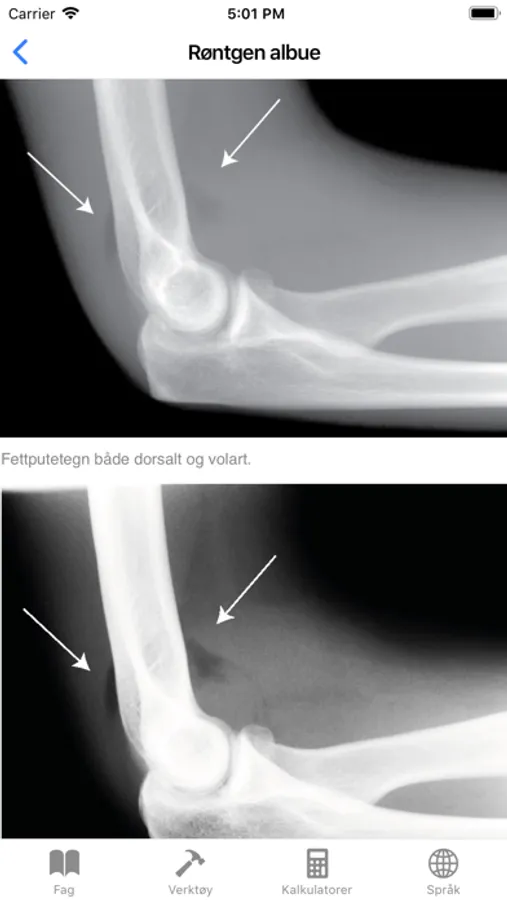

Røntgen albue